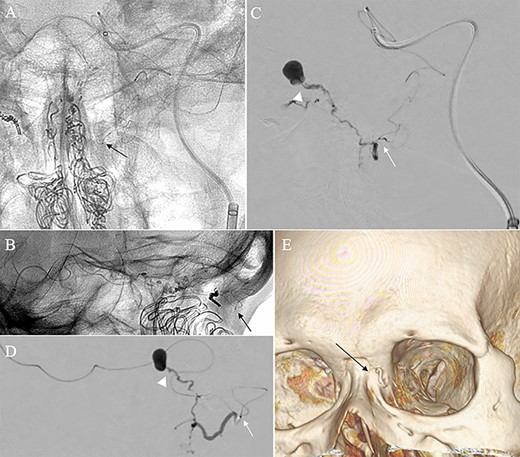

A patient in their 70s with extracranial lymphoma was incidentally found to have ACF–dAVF via head computed tomography and magnetic resonance angiography. Digital subtraction angiography (DSA) confirmed ACF–dAVF with multiple feeding branches, arising from bilateral OphAs, distal IMAs and the left middle meningeal artery (MMA), with cortical venous reflex (Borden type III, Cognard type IV) (Fig. 1). At the patient’s request, we chose endovascular, rather than surgical, treatment. We injected a 20% N-butyl-2-cyanoacrylate (NBCA)–lipiodol mixture into the fistula through bilateral ethmoidal arteries and the left MMA after we placed coils at the terminal branch of the right OphA. However, we could not achieve full penetration into the fistulous connections because of pressure secondary to high flow from the IMA branches, which resulted in incomplete obliteration (Fig. 1). Four months later, we repeated TAE by temporarily reducing nasal blood flow by inserting gauze infiltrated with xylocaine and epinephrine into the nasal cavities. After introducing the guiding catheter, an endonasal surgeon inserted X-ray-detectable surgical gauze infiltrated with 1% xylocaine and epinephrine (1:10 000) into bilateral nasal cavities using a nasal speculum, while paying full attention to avoid damage to the nasal mucosa. Then, we confirmed that the gauzes were placed in appropriate locations in the upper nasal cavity under fluoroscopic guidance. Immediately after insertion, we were able to confirm decreased blood flow from the IMA using DSA (Fig. 2). After this procedure, we navigated a DeFrictor Nano Catheter (Medico’s Hirata, Osaka, Japan) into the terminal branch of the OphA, which was connected to the dorsal nasal artery. Even though there was still a distance from the tip of the microcatheter to the shunt pouch, the NBCA reached the shunt point and penetrated the venous portion (Fig. 3). Follow-up DSA demonstrated complete obliteration of the ACF–dAVF, and blood flow in the nasal mucosa from the IMA branches recovered normally (Fig. 4).

Right (A) and left (B and C) internal carotid artery angiography before initial treatment showing ACF–dAVF with feeding arteries arising from branches of the OphAs; ethmoid artery (arrow) and dorsal nasal artery (arrowhead) (D and E). Bilateral external carotid artery angiography before initial treatment, anteroposterior view, showing the ACF–dAVF fed by bilateral distal internal maxillary arteries and the left middle meningeal artery.